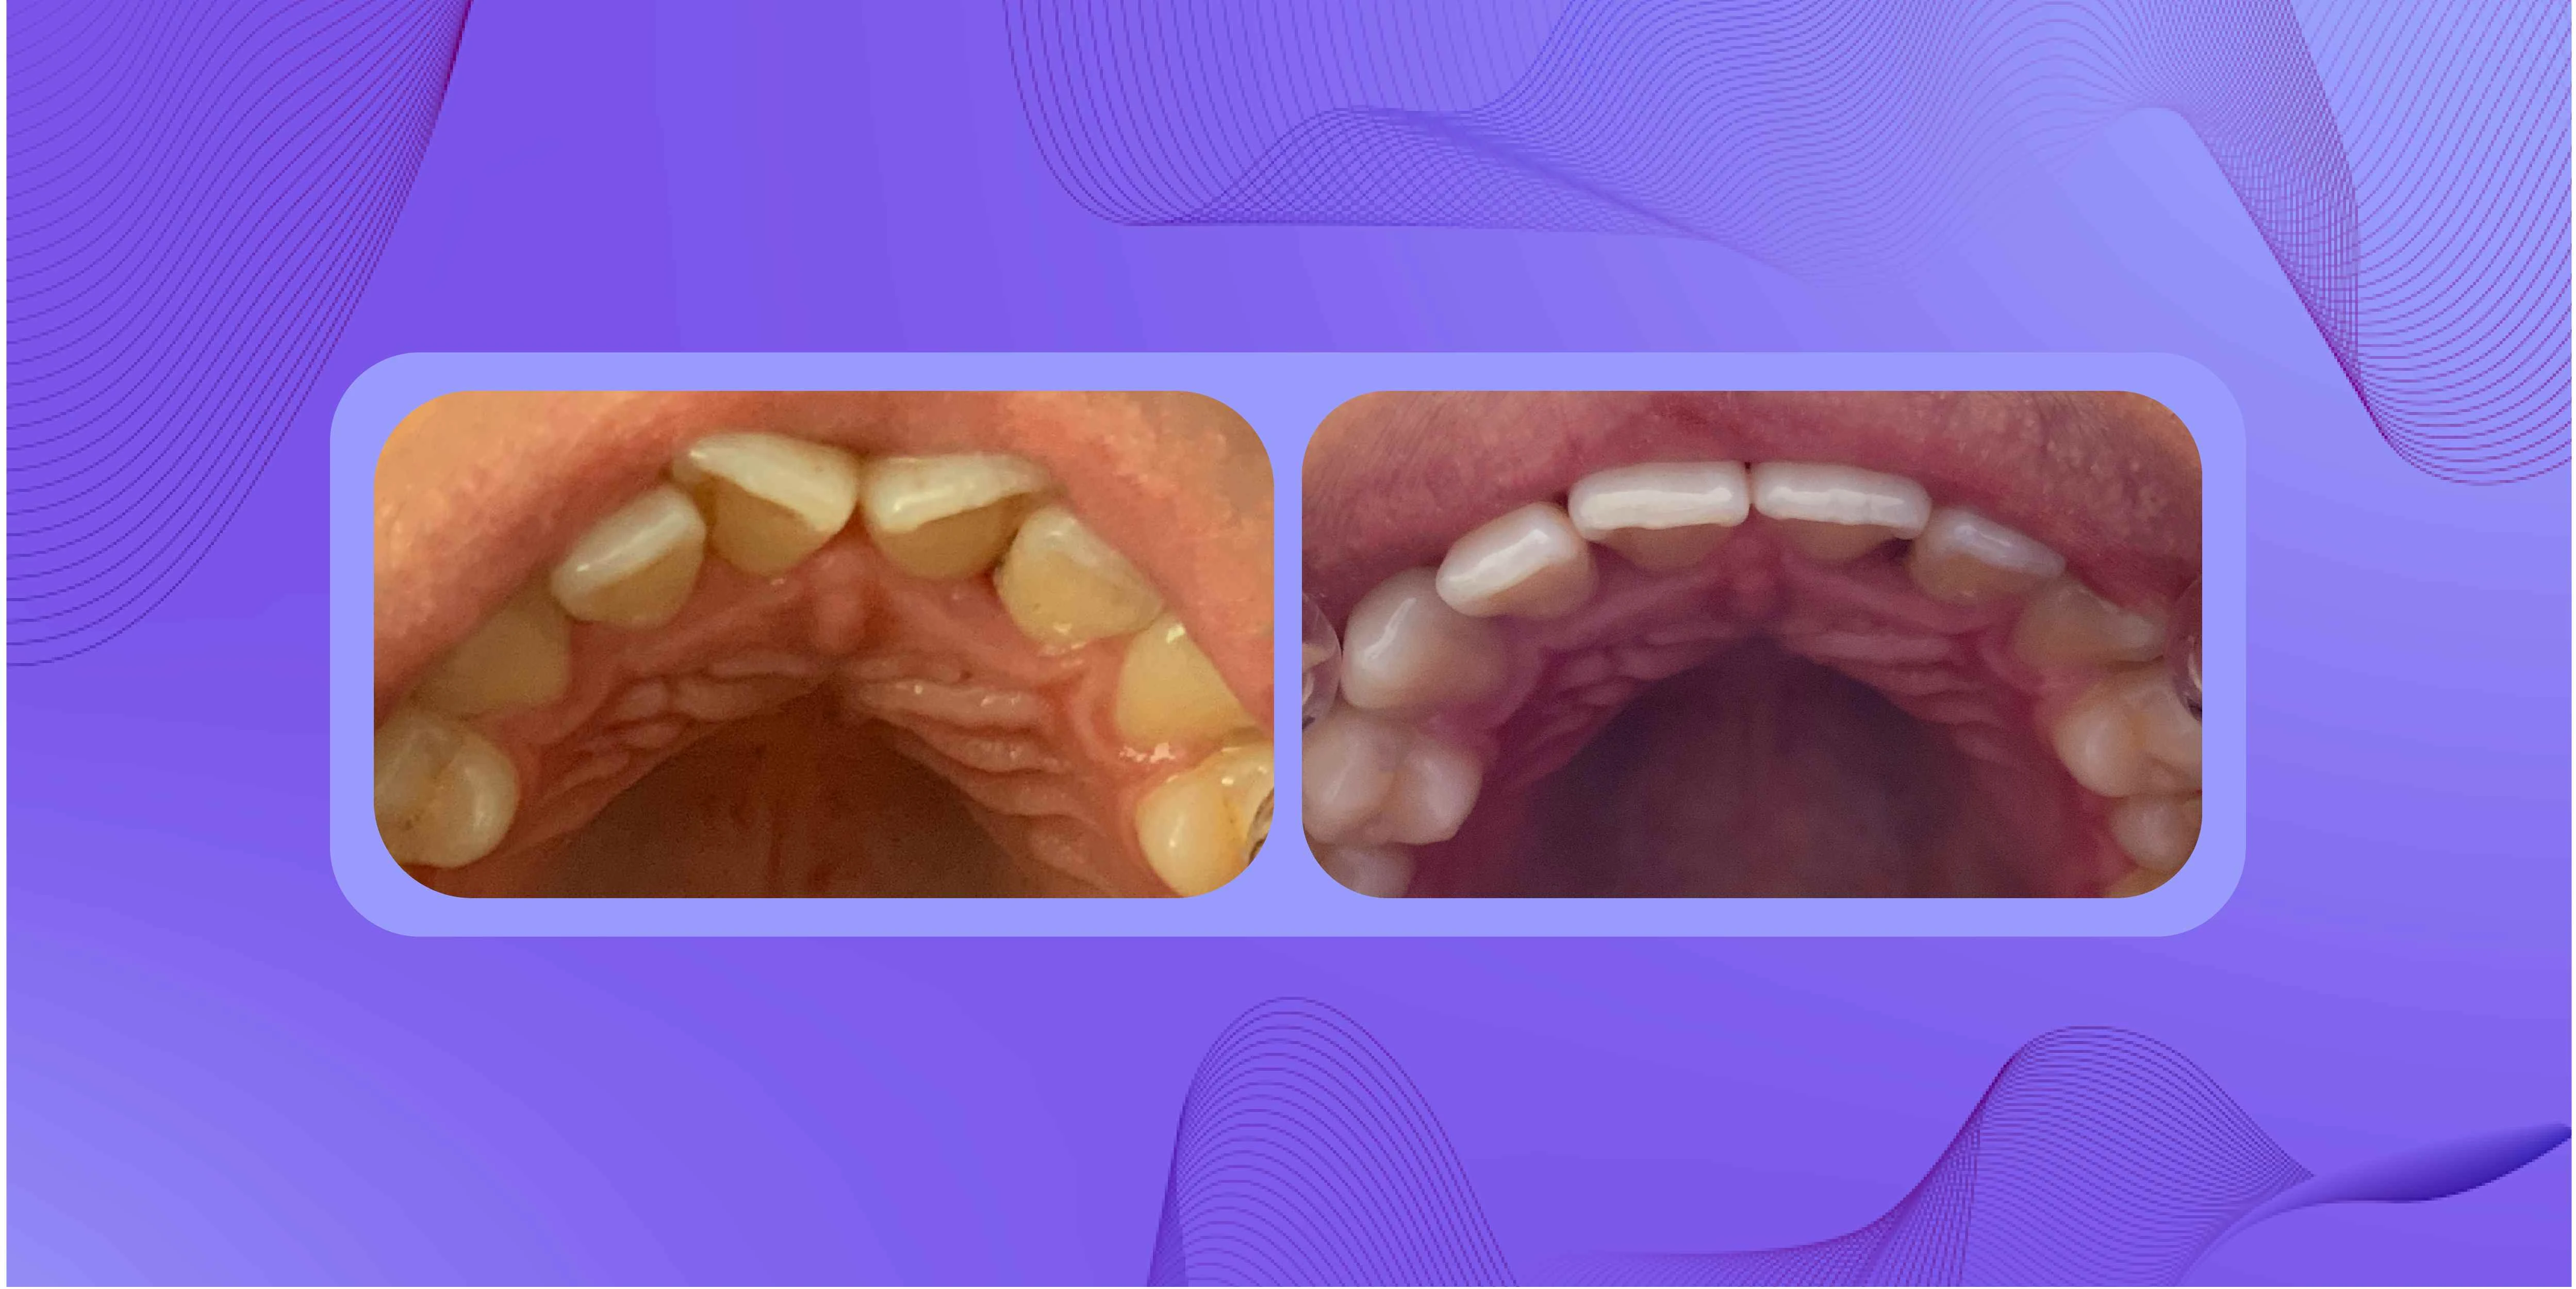

Apiñamiento dental

Este es uno de los casos más comunes y frecuentes dentro de la odontología y ocurre cuando dos o más dientes se amontonan debido a la falta de espacio en alguna de las arcadas (grupo de dientes que dan forma a la mandíbula). Dependiendo de su nivel podrá ser tratado con los **alineadores invisibles. **

Antes y después de un paciente con apiñamiento dental.